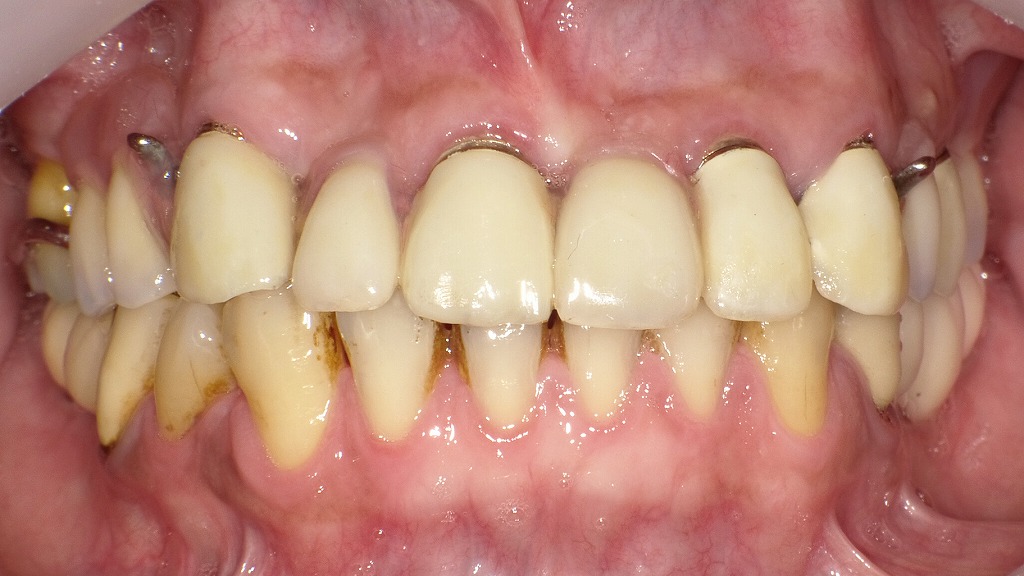

🔸 義歯装着後の状態

義歯(外冠付き)を装着した状態です。

見た目は非常に自然で、金属のバネが一切見えません。

- クラスプがないため審美性が高い。

- 金属床により軽くて丈夫。

- 熱伝導性がよく、食事の温度を自然に感じられる。

- 内冠と外冠の摩擦力で、安定感が非常に高い。